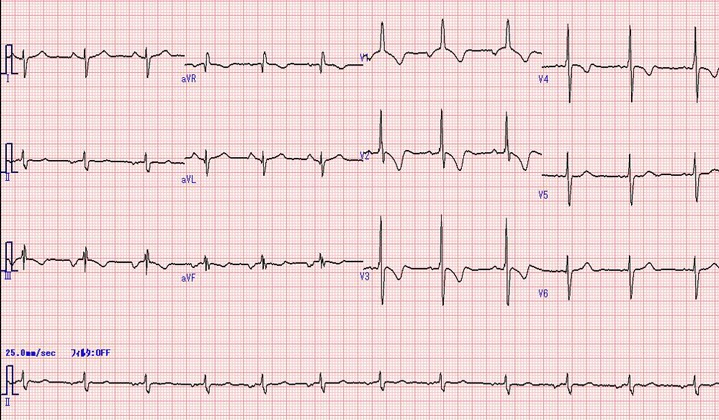

心電図は、異所性心房調律と典型的な右室肥大である。

このような典型的な右室肥大の所見は、先天性心疾患に特徴的である。特にチアノーゼ、手指の太鼓バチ指を認めることから、ファロー四徴症、完全大血管転位症、修正大血管転位症、両大血管右室起始症、エプスタイン奇形、総肺静脈潅流異常症、三尖弁閉鎖症などが考えられる。